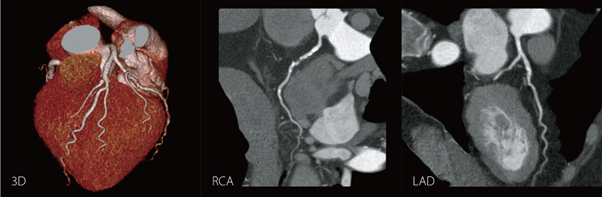

Đặc biệt, thế mạnh của máy CT 160 lát cắt Aquilion Prime SP là khả năng chụp tim – mạch vành và đồng bộ nhịp tim. Công cụ SURECardio thông minh được mã hóa với kinh nghiệm của hàng nghìn ca khám tim, đảm bảo các thông số quét thích ứng chính xác với bệnh nhân cho phép chụp và dựng hình hình ảnh tim – mạch vành ngay cả với những bệnh nhân có rối loạn nhịp tim như ngoại tâm thu, nhịp nhanh, loạn nhịp,… Đây là một phương pháp khảo sát hệ thống mạch vành để chẩn đoán hẹp, xơ vữa một cách chính xác mà không cần xâm lấn.

Hình ảnh dựng hình tim và mạch vành của máy Aquilion Prime SP